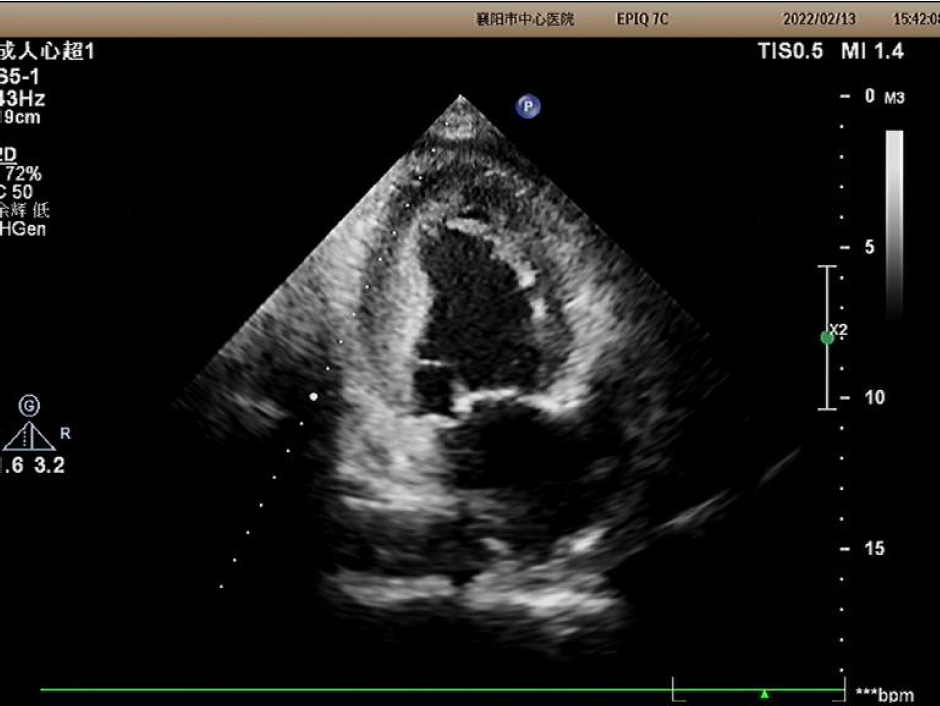

2022年2月13日超声图像

主动脉瓣峰值流速:4.59M/s;

升主动脉内径:55mm;

平均跨瓣压差:84mmHg;

左室射血分数EF值:46%;

主动脉瓣增厚,回声增强,瓣叶形态显示不清,瓣膜开放明显受限;

升主动脉瘤形成;心包积液;

主动脉瓣口左室流出道侧见舒张期轻度反流信号。

诊断:主动脉瓣重度狭窄。经团队讨论和患者家属商议后决定,行TAVR手术治疗。